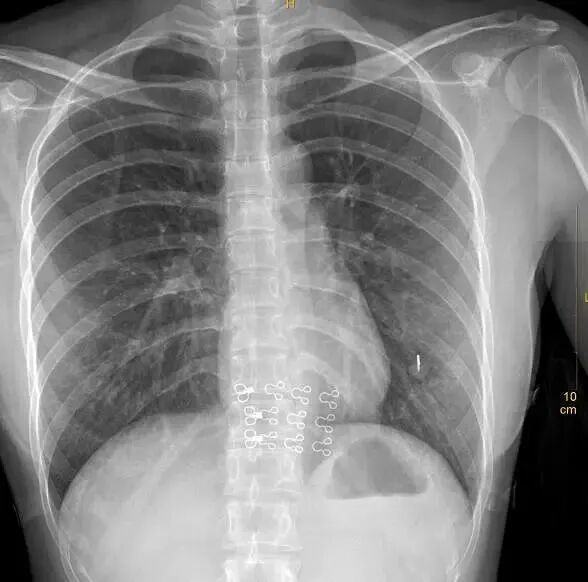

这是带有伪影干扰的胸片

①这个文胸结构比较复杂……